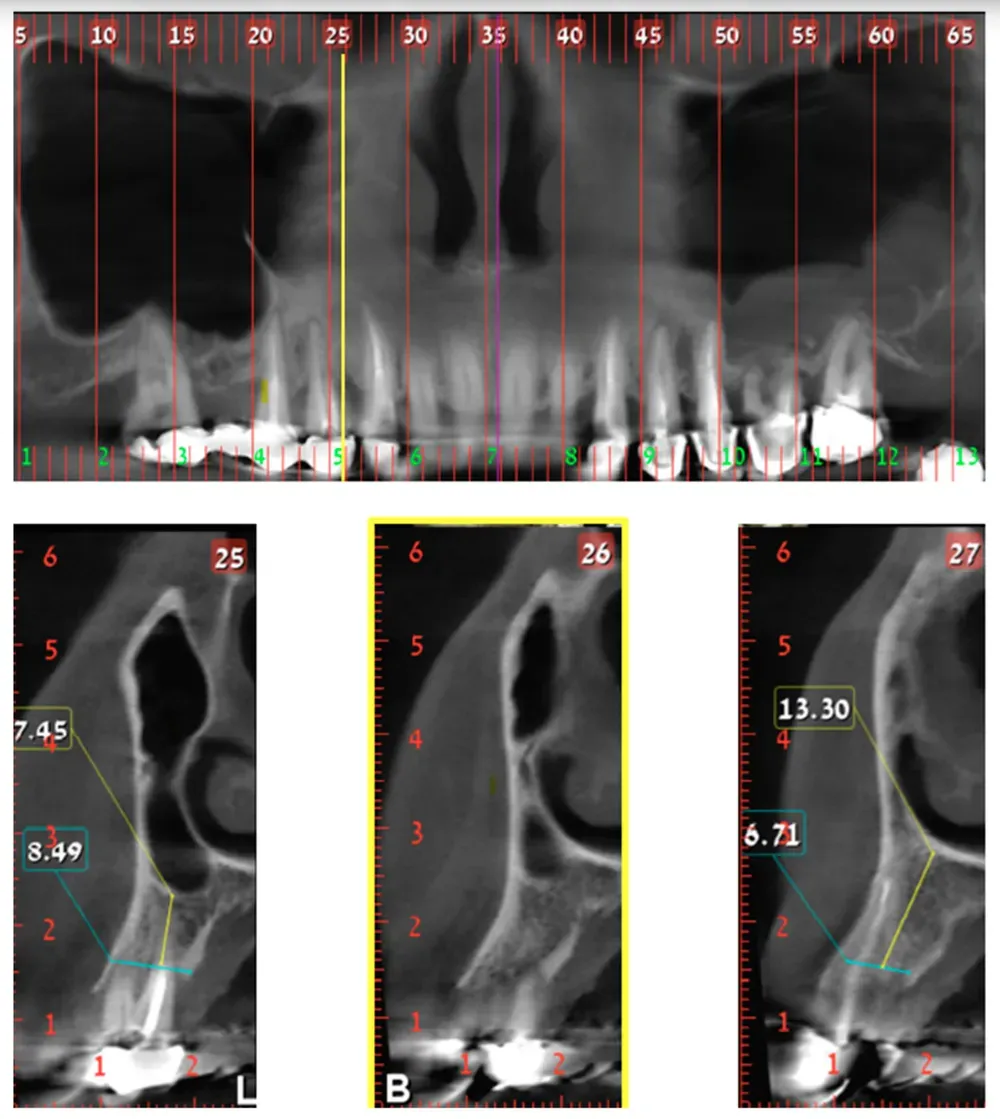

Classe 2 della variante big nose del seno mascellare

Classe 2

Classe 3 bilaterale della variante Big nose del seno mascellare

Classe 3 bilaterale